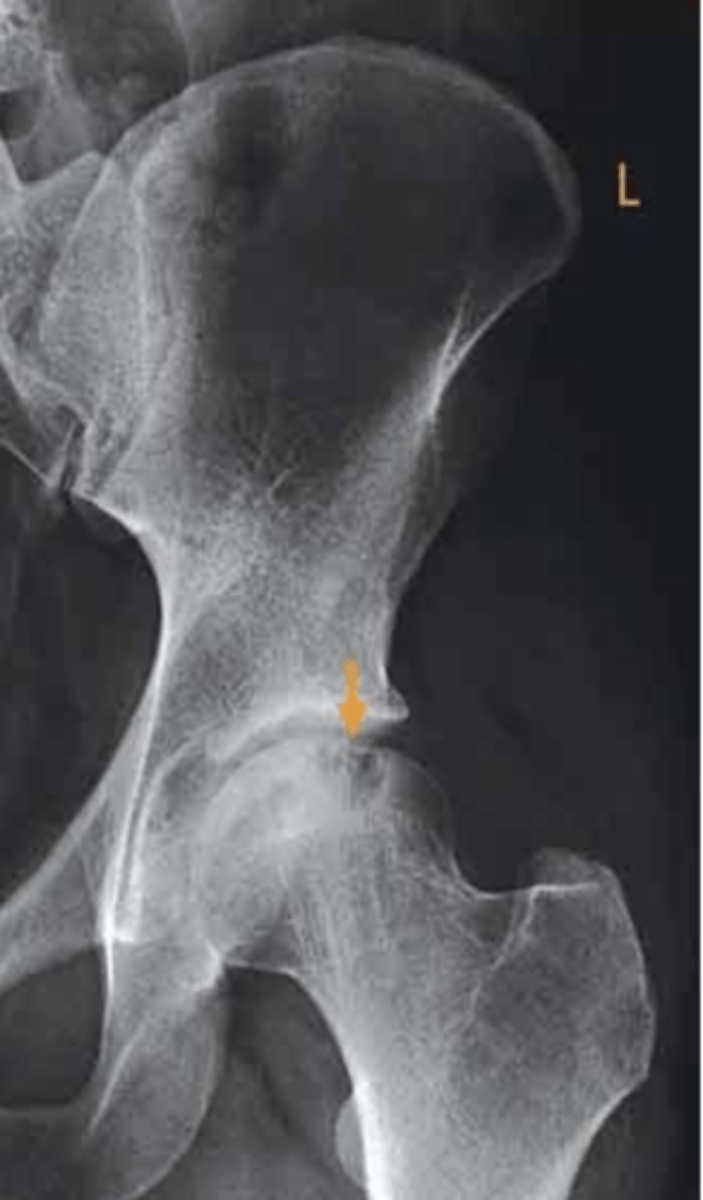

what view is this radiograph?

anteroposterior

what structure is indicated by the orange arrow?

osteochondral fracture of the left femoral head